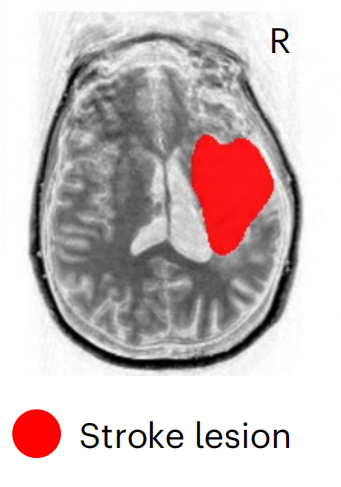

病例1:女,31歲,在參與該研究的九年前,因海綿狀畸形繼發(fā)于右側(cè)丘腦出血性中風,病變局限于內(nèi)囊、中腦和腦橋,F(xiàn)AS=0.17,F(xiàn)ugl-Meyer運動評估顯示中度損傷。 病例2:女,47歲,在參與本研究的三年前,因右頸動脈夾層導致右側(cè)缺血性大腦中動脈(MCA)卒中,導致大面積MCA梗死。SCS01的,病變范圍較大,影響右半球的放射冠,F(xiàn)AS=0.35,F(xiàn)ugl-Meyer運動評估顯示重度損傷。 SCS01 SCS02 治療方案